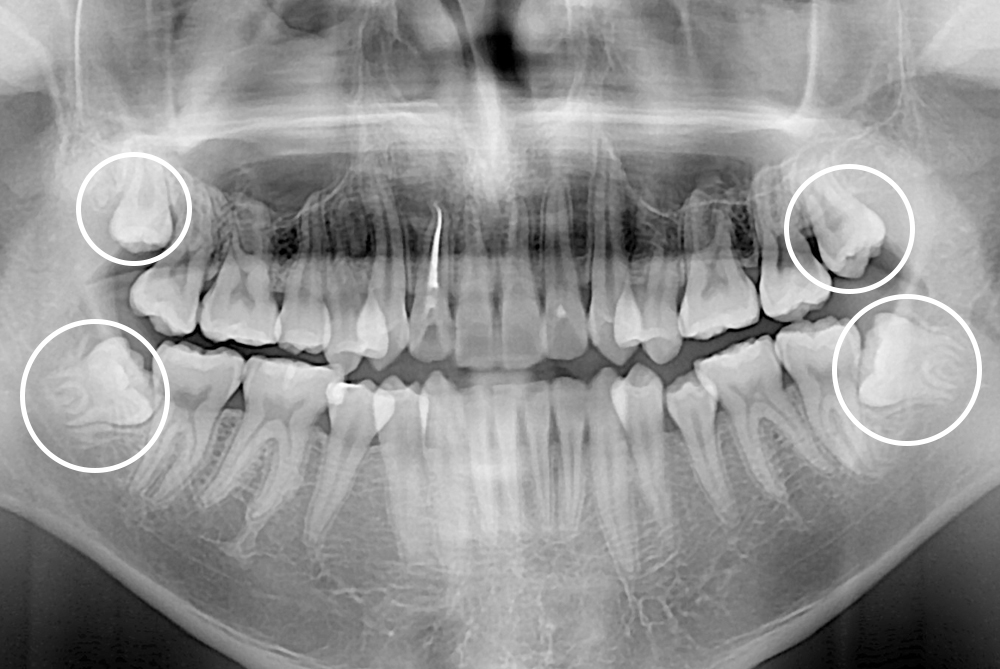

[사랑니] 매복 사랑니 발치

치료전 : 2021-01-04

세종치과는 구강악안면외과학 박사이신 원장님이 발치하는 치과입니다.